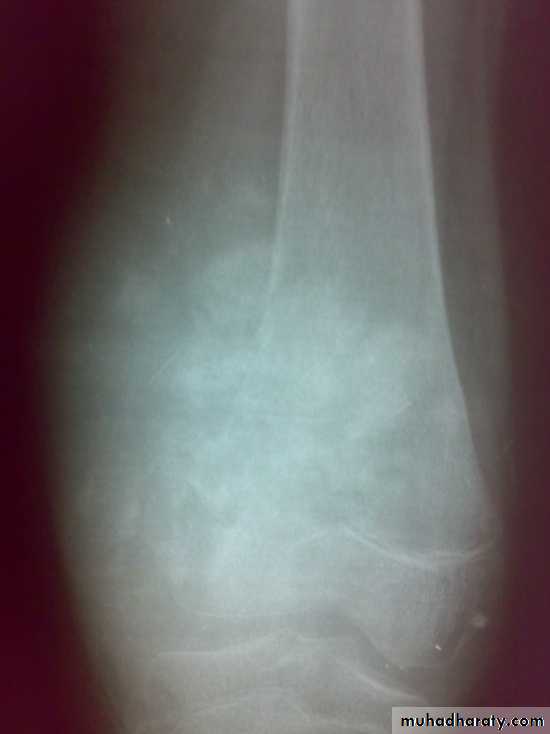

Giant cell tumor

X-ray show eccentric osteolytic lesion in the end of long bone ,subchondral, trabeculated (soap bubble appearance). The cortex is thin, expanded or even perforated.